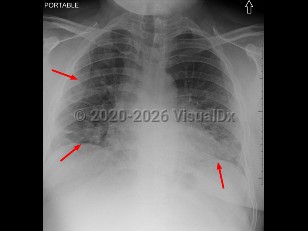

Acute radiation syndromeAcute radiation syndrome

Acute radiation enteritis